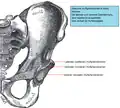

Anatomische Besonderheiten

- Beckenanatomie

Anatomie des gesunden Beckens (Ansicht von vorne) -

Das Becken ist der Mittelpunkt des menschlichen Körpers und vereinigt die Wirbelsäule mit der unteren Extremität (Bein). Gleichzeitig liegen wichtige Organe, wie z. B. die Harnblase, der Enddarm, die Geschlechtsorgane und deren Anhänge, direkt im Beckengewölbe. Große Gefäße und Nerven (Ischiasnerv, Beckenarterie und -vene) gabeln sich hier. Schließlich setzen zahlreiche Muskeln, Sehnen und Bänder am Becken an, die für die Körperstatik und besonders für die komplexen Hüftbewegungen wichtig sind.

Die gewölbeartige Struktur des Beckens und die empfindlichen Weichteilverhältnisse (Nerven, Gefäße, Muskel-Sehnenansätze) machen die Zugangswege kompliziert.